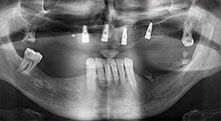

Брату: Ние използваме инструментите за събиране на костни блокове и разделяне на алвеоларни гребени. Ние също използваме Piezomed B6/B7 за остеотомия на наранени зъби и отстраняване на неуспешни импланти. Всички индикации, които изискват дълбоки, чисти разрези.

Брату: Ние предпочитаме да събираме кост от външната страна на гребена в задната част на долната челюст. След разрязване на меките тъкани, ние използваме новите триони, за да определим количеството кост, което ще събираме. С този подход, ние използваме трионите за цялата препарация в почти 80% от случаите. Може да използваме и други пиезо инструменти и накрая длето за мобилизиране на блока. Ние смятаме, че това е изключително ефективна хирургична техника.

Брату: Ние предпочитаме да използваме техниката "сандвич" за аугментация в страничната долна челюст. Покритие на костта се подготвя с пиезо трион и кресталният фрагмент се фиксира с микровинтове. Поставяме смес от автогенна костна присадка и ксеногенен костозаместител между тях. Това работи много надеждно. Трябва винаги да осигурявате достатъчно оразмерени вертикални срезове при шиниране на алвеоларния гребен в долната челюст. В противен случай, костта лесно може да бъде счупена.